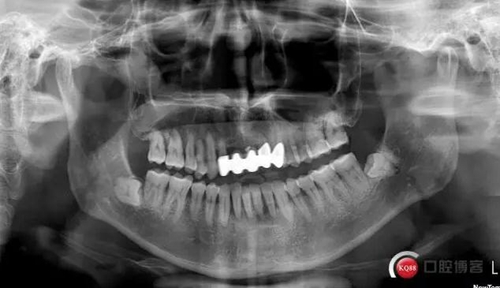

檢查:口腔衛(wèi)生狀況欠佳,牙面可見大量色素附著,牙石II°,尤以下頜前牙舌側(cè)及后牙頰側(cè)為重。牙齦紅腫,BI3-4°,PD下頜前牙區(qū)4-6mm。31松動III°,溫度測試無反應,叩不適。32、41、42松II°+,32溫度測試遲鈍,叩(-)。

X線示牙槽骨吸收,下頜前牙區(qū)可見齦下牙石影像,牙槽骨吸收至根尖1/3,根周透射影像。